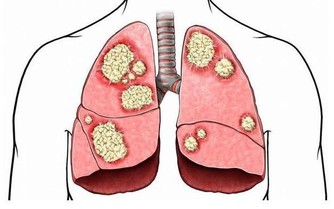

牙周病,是指發生於牙齒支持組織(牙周組織)的疾病,它分為兩類:一類是累及牙齦組織的牙齦病,另外一類是波及深層牙周組織(牙周膜、牙槽骨、牙骨質)的牙周炎。

牙周病是最為常見的口腔疾病,是引起成年人牙齒壞死的主要原因之一,是危害牙齒健康的主要口腔疾病。它不僅會損害牙齒,影響牙齒的完整和美觀,還會損害咀嚼功能,甚至還會對全身的健康造成威脅。

該病可怕之處在於掉的往往不是一顆牙,而是一組牙,整排牙,甚至是全口牙!要知道,牙周是牙齒賴以生存的土壤,如果水土都流失了,樹木又長在哪兒呢?

牙周病的病因很多,最主要是口腔衛生做得不夠,導致局部的牙菌斑(指黏附於牙表面的微生物群,不能用漱口、水沖洗等去除,是牙周病的主要致病因素)、牙石(沉積在牙面上的礦化物質)、食物軟垢等物質堆積,長期刺激牙周,導致牙周組織發生炎症,最後形成慢性炎症,並且還誘使牙槽骨吸收、牙根外露、牙齦萎縮,最終導致牙齒鬆動、脫落。